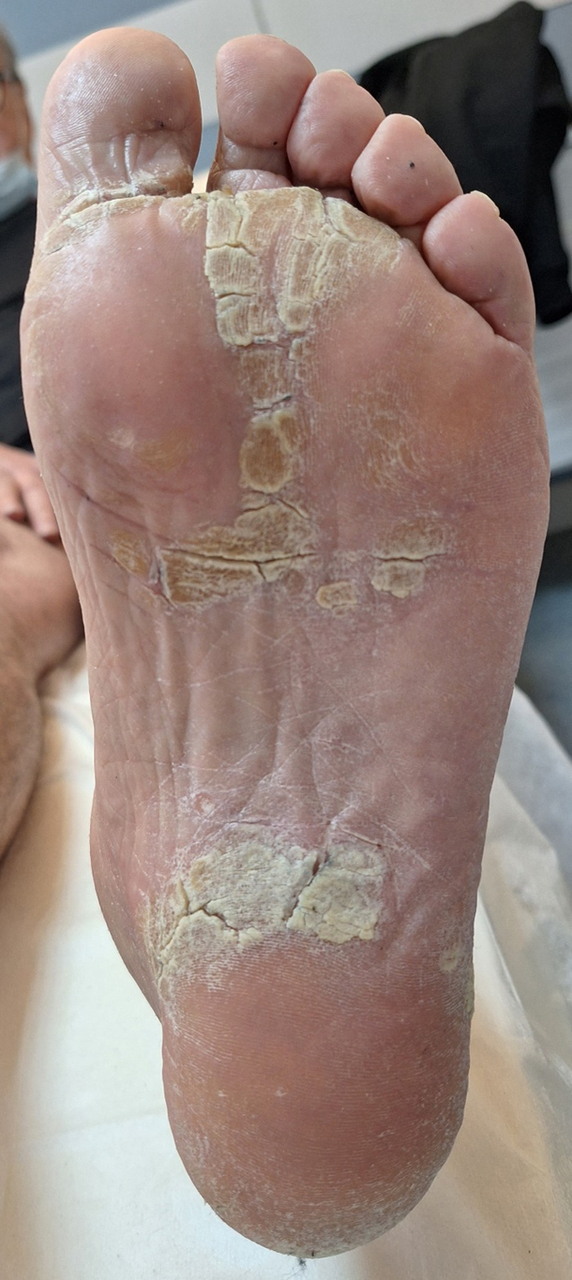

Le patient revient une semaine plus tard avec les examens prescrits. Biologie : hémoglobine = 13,4 g/dL ; leucocytes = 9 G/L avec formule leucocytaire normale ; plaquettes = 238 G/L ; aspartate aminotransférase (ASAT) 24 UI/l ; alanine aminotransférase (ALAT) = 25 UI/l ; gamma-glutamyl transférase (GGT) = 84 UI/L ; phosphatases alcalines (PAL) = 226 UI/L ; bilirubine totale = 8 µmol/L ; créatinine = 81 µmol/L, soit un débit de filtration glomérulaire (DFG) à 96 mL/min ; protéine C réactive (CRP) = 14 mg/L ; uricémie = 401 µmol/L ; facteurs antinucléaires (FAN) = 1/80 ; facteurs rhumatoïdes (FR) et anti-peptides cycliques citrullinés (anti-CCP) négatifs. Ponction du genou : 8 600 éléments, pas de cristaux, culture négative à 48 heures. Les radiographies des genoux sont normales, notamment pas de pincement, pas d’érosion, pas de méniscocalcose. Les radiographies des pieds sont les suivantes : Figure 3 (Source : Salomé Abdellaoui, La Revue du Praticien) L’échographie des pieds confirme la dactylite du 3e orteil droit et ne retrouve pas d’autre anomalie.

L’association d’une oligo-arthrite chronique, d’une dactylite, et d’un psoriasis oriente vers le diagnostic de rhumatisme psoriasique. Les radiographies des pieds sont normales à l’exception d’un ostéophyte de la dernière phalange du premier rayon droit, évocateur d’arthrose. Dans le rhumatisme psoriasique évolutif, il est classique de retrouver des lésions destructrices et reconstructrices. Les autres diagnostics sont beaucoup moins probables devant l’absence de marqueurs d’auto-immunité, de cristaux à la ponction, d’érosions caractéristiques radiographiques.

Les radiographies ici sont normales et n’orientent donc pas le diagnostic.